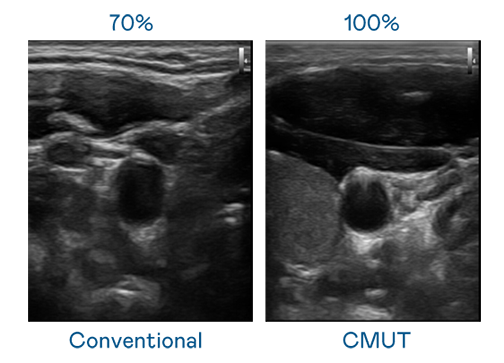

CMUT 技术是一种用电容式微机电元件来产生超音波讯号的技术。与传统 PZT 压电式技术相比,CMUT 频宽增加 30%,更宽频的超音波讯号让影像解析度大幅提升,是实现高影像品质医疗超音波扫描、促进精准医疗发展的关键技术。

大频宽带来超清晰影像

超音波影像的解析度高低,首先取决于探头能发出的讯号频宽。PA旗舰厅 CMUT 可提供高清晰的超音波讯号,提供高频宽、高灵敏度、影像纹理细节更高的超音波影像,协助医护人员缩短影像判读时间及利用精准的医疗影像进行诊断。